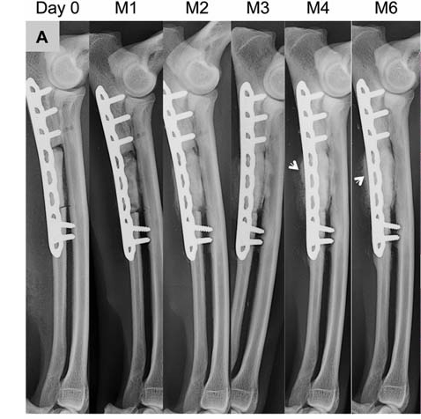

兔骨折模型

兔骨折模型模型